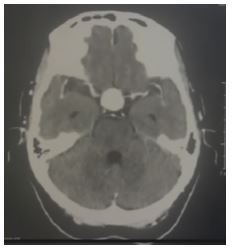

Imaging tests: CT scans revealed a saccular aneurysm of the right supraclinoid internal carotid artery associated with bone remodeling (Figures 1 and 2). On the other hand, magnetic resonance imaging (MRI) of the pituitary showed a saccular aneurysmal dilation occupying the sella turcica with suprasellar extension, originating from the right internal carotid artery.

Figure 1. Contrast-enhanced CT scan of the brain showing a saccular aneurysm